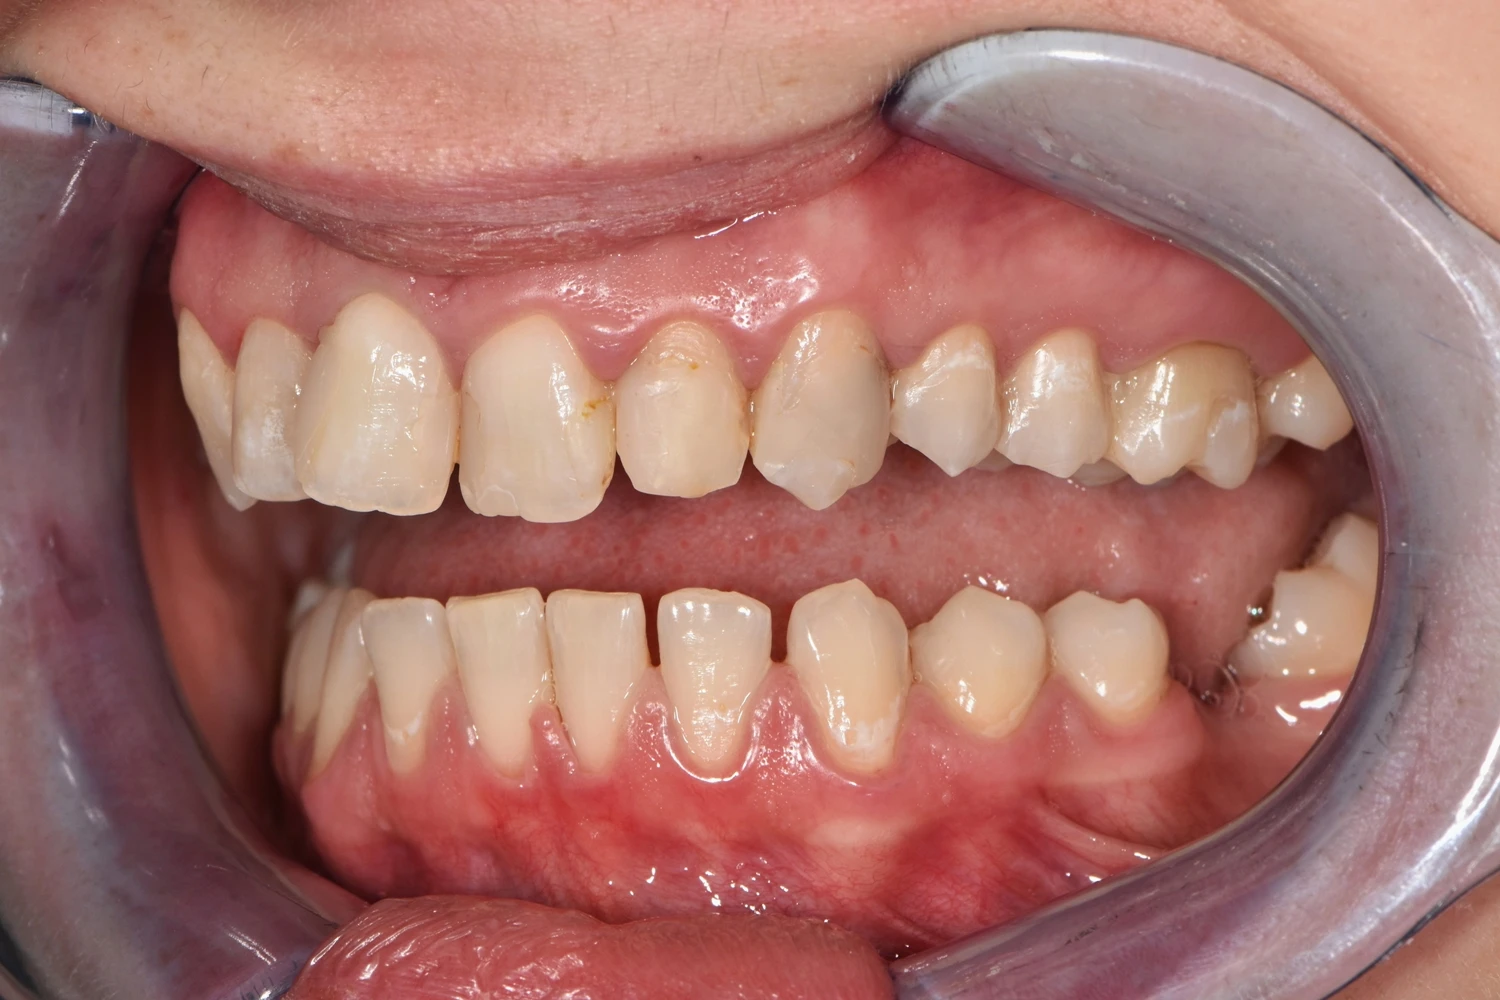

Caz de reabilitare totală orală.

Provocarea acestui caz a fost in reabilitarea totală a pacientului atâta a maxilarului superior cat și a mandibulei, tratând absolut toți dinții prezenți și reconstruindu-i cu pivoți de fibră de sticlă pentru a putea obține o susținere suficientă pentru viitoarele coroane.

Grupul superior fiind distrus complet, am efectuat tratamente la microscop, reconstrucția individuală a fiecărui dinte, tratamente parodontale cu laser pentru sănătatea ginigivala și am optat pentru coroane individuale de zirconiu ceramică pentru un plus de duritate și protecție a dinților cat și pentru o estetică frumoasă. Au fost folosite un set de provizorii de lungă durată pentru reechilibrarea articulației și muscaturii.

Pacientul a beneficiat inferior de igienizare în profunzime , detartraj și airflow, tratamente endodontice , obturații ( plombe) , tratamente parodontale cu laser iar în final punți și coroane individuale de zirconiu ceramica.

Termen de finalizare 2 săptămîni de la amprentarea finală.